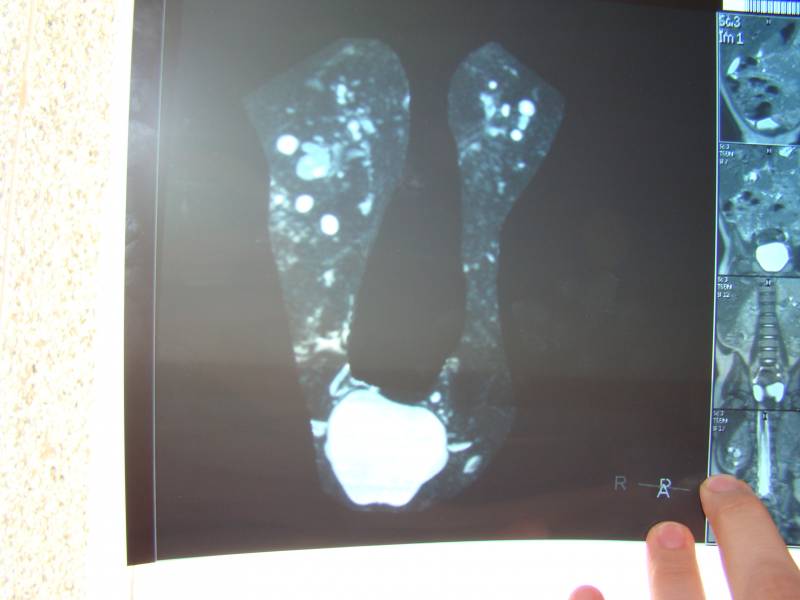

снимки